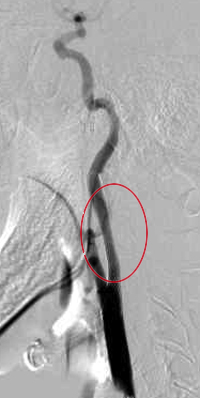

ステント留置の手術前

ステント留置の手術後